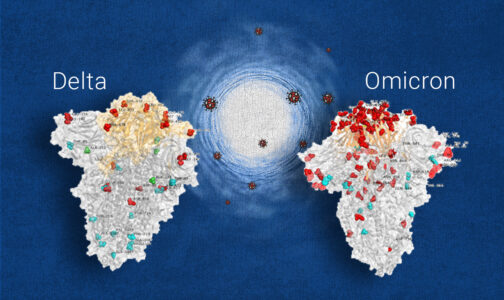

Ο ίδιος είπε ότι μέχρι στιγμής δεν γνωρίζουμε τα δεδομένα για τη μεταδοτικότητα της μετάλλαξης, ενώ υπάρχουν πολλά κενά και σχετικά με τη νοσηρότητα. «Το εμβόλιο είναι πολύ πιθανόν να παρέχει ανοσία σε έναν βαθμό και έτσι παραμένει ένα πολύτιμο εργαλείο», είπε ο κ. Ζαούτης.